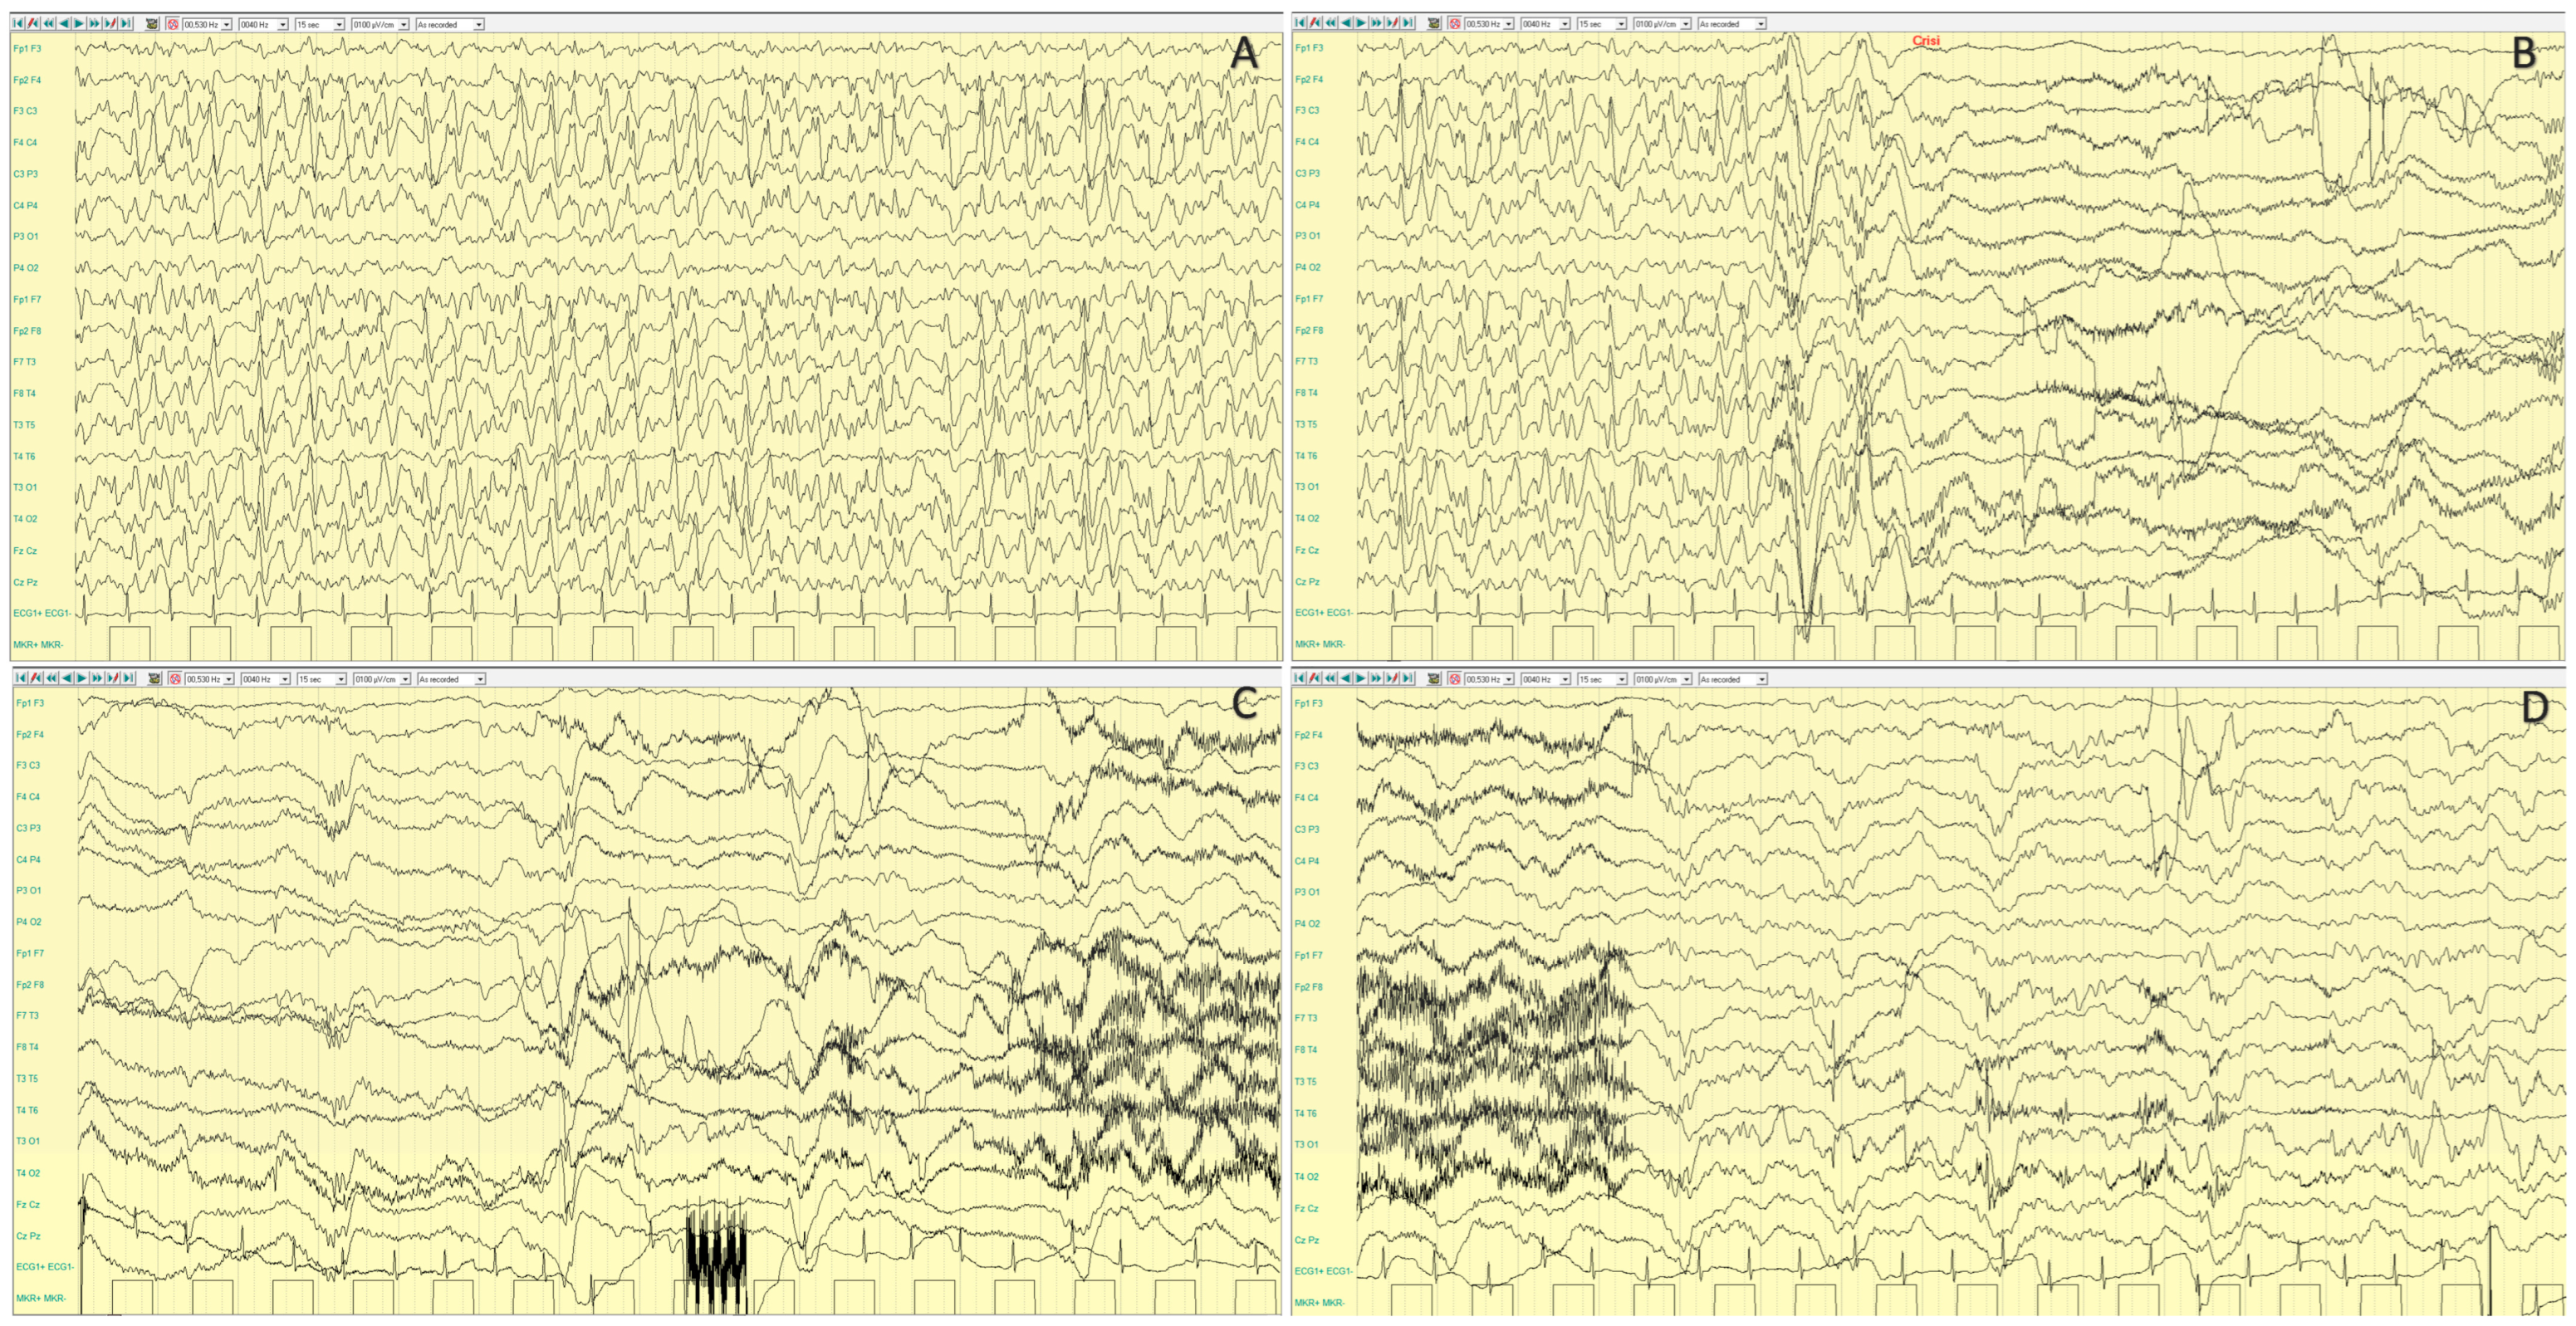

4.2.2. Epileptic Phenotypes

4.2.3. Neurocognitive Profile and Other Disorders